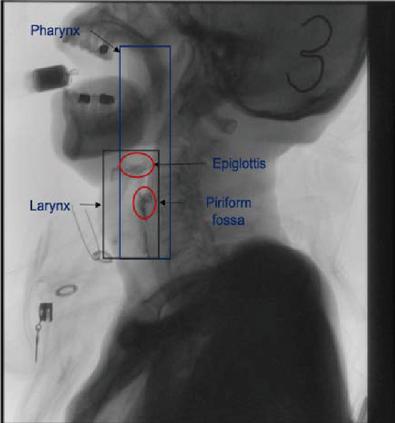

images

Figure 2 This case demonstrates a simplified procedure for the extraction of a patient’s piriform fossa.

The premise of our work is to judge a single frame from the original barium recognition, and gradually transfer to the determination of tissues and organs through the barium recognition. Why accurate tracking, only the complete track of barium agent, to facilitate the later determination of barium agent in each organ stay position, time and quantitative study. We used morphological methods to extract barium. Due to the quality difference of the original film, the expected errors of the barium trace area deviation in this experiment were within -25%25%.